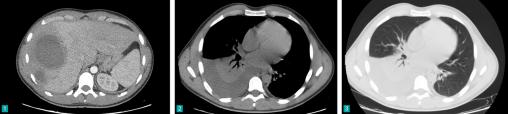

Erwan Le Dault, La Revue du Praticien Scanner thoraco-abdomino-pelvien Extrait de : Dossier progressif n°152